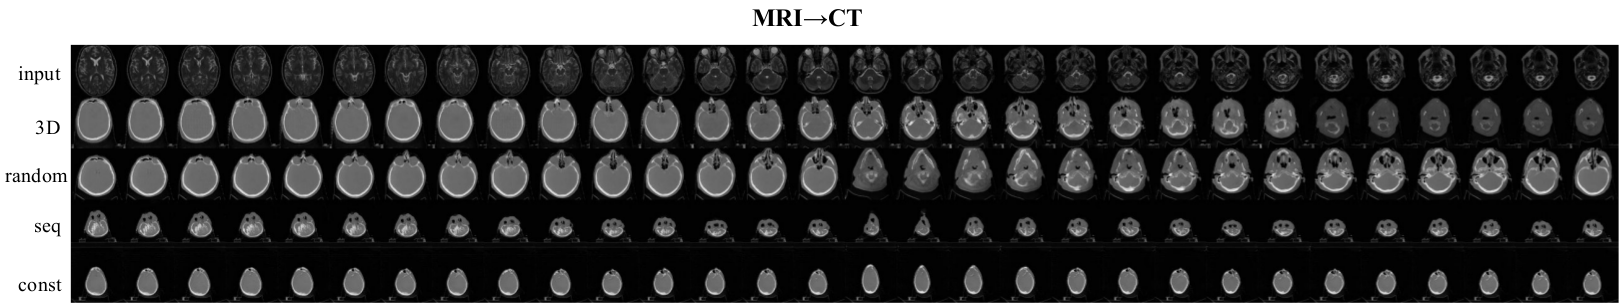

The experiments on MRI-to-CT translation showed that all per-frame translation methods produce image volumes that do not capture the real anatomy (e.g. shape of the skull, nasal path and eyes vary significantly within the neighboring frames), whereas the proposed 3D method gives a continuous and generally more realistic results for both CT-MRI and GTA segmentation-to-video tasks (Table 4). The CT-to-MRI task is harder since it requires “hallucinating” a lot of fine details and on this task 3D model outperformed random with a significant margin (bold numbers). On a simpler MRI-to-CT task random and 3D models performed similarly within the limits of statistical error.

In contrast to the common practice, the sequential batch approach produced more realistic and continuous results compared to the random batch choice. Supposedly this is due to the fact that images within the sequence are more similar than randomly selected images, and hence the magnitude of the sum of gradients might be higher resulting in faster convergence. Of course, order of frames within sequential batch does not matter since all gradients are summed up during backward pass, but the similarity between images within a batch is important.